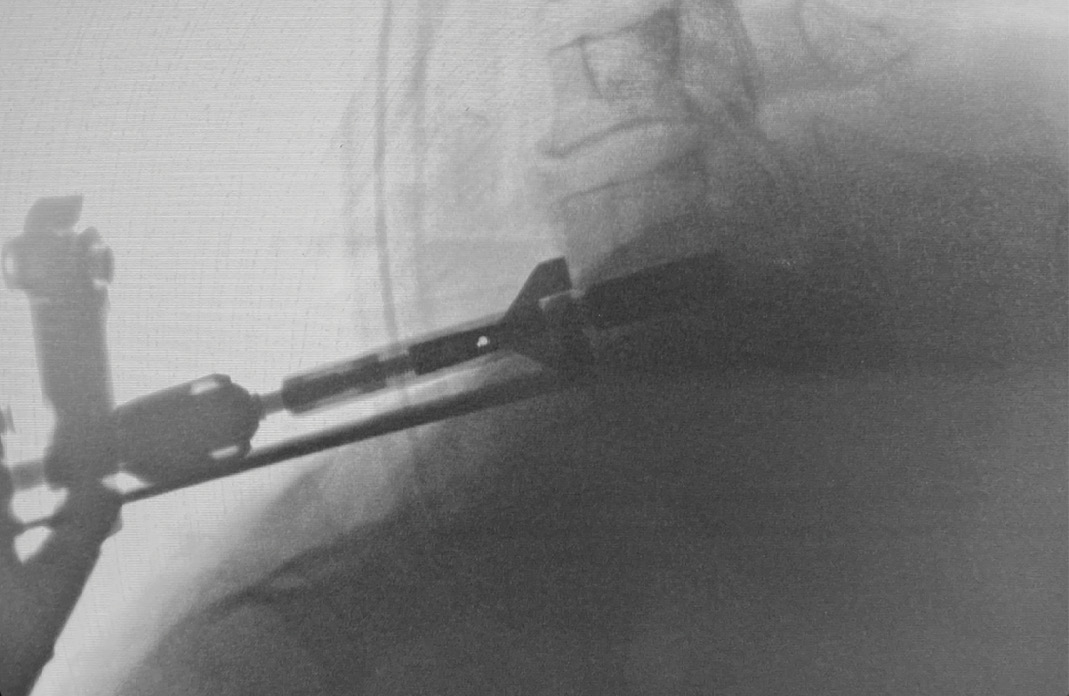

During intra-operative trialing after discectomy and foraminotomies, I felt that the best fit at the C6-7 level was with a prodisc C SK—6mm tall by 18mm deep (Figure 6a). I then performed the discectomy and trialing at the C5-6 level and felt that the prodisc C Vivo was a perfect fit here (Figure 6b).

The patient’s height likely contributed to needing a 6mm size. About 25% of the time, I find I need to bump up to a 6mm implant—but, ultimately, I base my decision upon what I see during trialing.